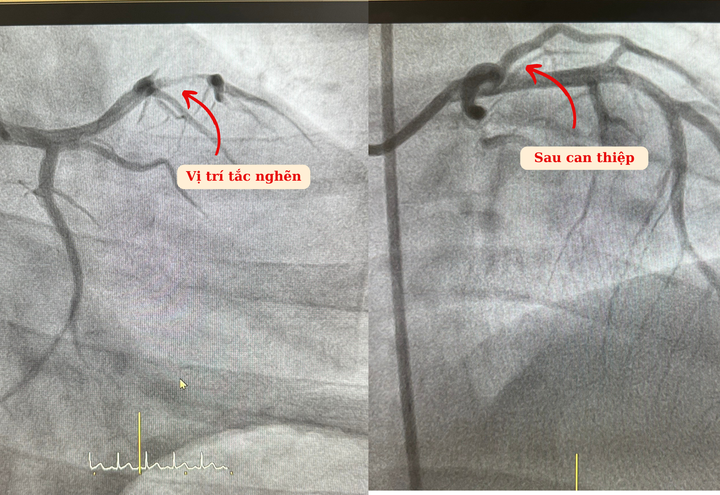

Bệnh nhân được chỉ định chụp mạch số hóa xóa nền (DSA) cấp cứu. Kết quả ghi nhận anh bị hẹp 99% động mạch liên thất trước - động mạch quan trọng nhất quyết định chức năng co bóp đưa máu đi nuôi cơ thể. Khai thác tiền sử cho thấy bệnh nhân có thói quen hút thuốc lá từ năm 12 tuổi, thường xuyên stress, thức khuya do tính chất công việc.

Ekip khẩn trương tiến hành can thiệp tái thông dòng chảy nuôi tim cho anh Tình.

Ths.BS Nguyễn Đình Công, khoa Tim mạch - Tim mạch can thiệp Hồng Ngọc - chia sẻ: “Nhận định đây là tình huống cấp cứu nguy hiểm, nếu không được can thiệp kịp thời có thể đe dọa tính mạng bệnh nhân, chúng tôi nhanh chóng tiến hành hút huyết khối và đặt stent để khơi thông dòng máu nuôi tim.”

Ca can thiệp kéo dài khoảng 60 phút, dưới sự hỗ trợ của máy chụp mạch số hóa xóa nền DSA hiện đại, bệnh nhân được đặt 01 stent kích thước 3.0 x 29mm vào vị trí hẹp động mạch liên thất trước. Kết quả ghi nhận từ máy siêu âm trong lòng mạch IVUS đánh giá stent nở và áp sát thành mạch, dòng chảy được khơi thông tốt. Các triệu chứng ban đầu được cải thiện rõ rệt. 24 giờ sau can thiệp, anh Tình có thể ăn uống và đi lại bình thường.

Hình ảnh kết quả trước và sau can thiệp của anh Tình.